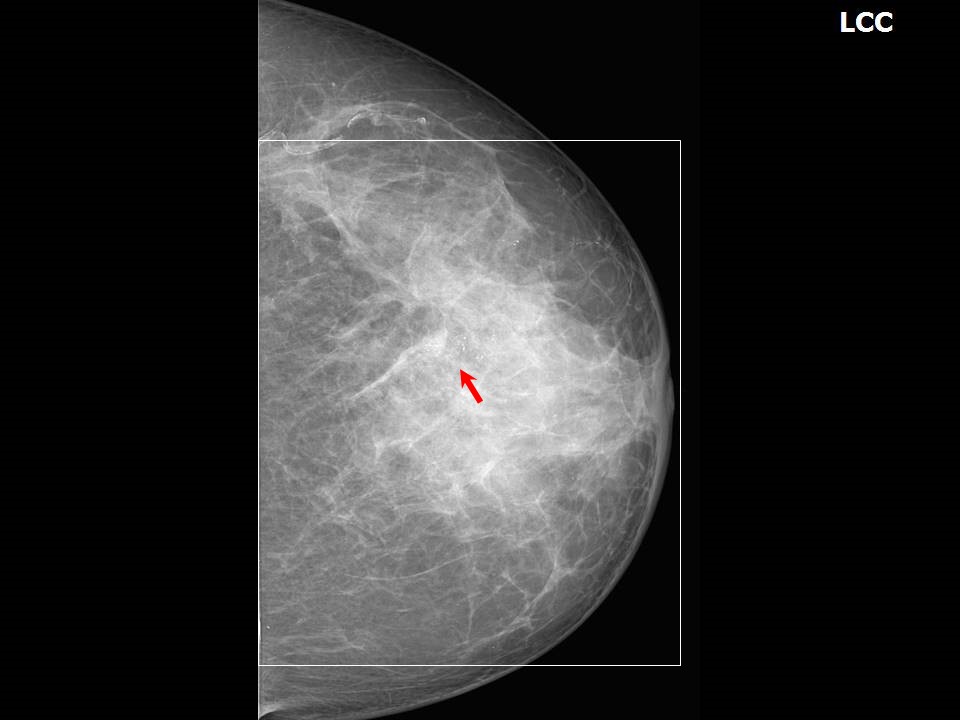

From www.researchgate.net

A mammogram of the left breast showed a left breast lesion with What Do Calcium Deposits In Breast Mean Breast calcifications are calcium deposits that are found in breast tissue and are fairly common, especially in women older than 50. As breast cells grow and divide, calcium deposits can build up in breast tissue. They appear as white spots or flecks on a mammogram. Breast calcifications are calcium deposits that develop in breast tissue. Called calcifications, these deposits can. What Do Calcium Deposits In Breast Mean.